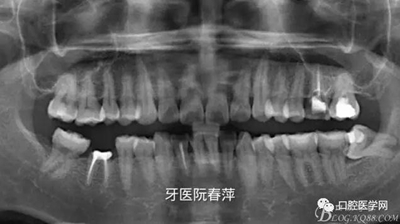

(5)X光片檢查:全景片看到25齲壞未近髓,26根管充填材料良好,27根管無充填材料,根尖區(qū)未見低密度影。

全景片如下圖

絢彩AT無飾瓷全形態(tài)氧化鋯產(chǎn)品體驗(yàn)+全冠和嵌體微創(chuàng)修復(fù)后牙當(dāng)時25和27無臨床癥狀均無做任何處理。由于考慮到26的牙體破壞面積大,固位抗力不佳,根管治療后纖維樁加固樹脂充填。